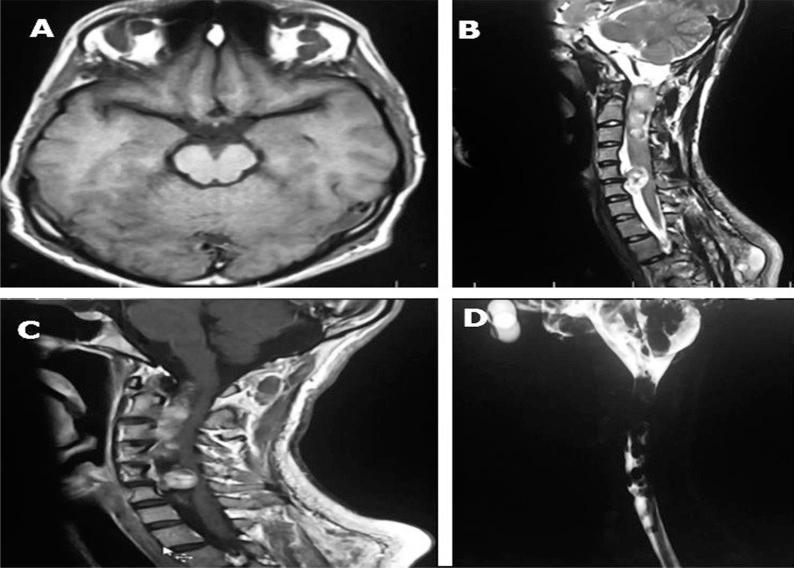

Neurofibromatosis type 1, presenting as a rare widespread neurofibromas with cord compression.

https://cdn.ncbi.nlm.nih.gov/pmc/blobs/8368/4852072/966e63eeec22/IJNL-15-57-g001.jpg